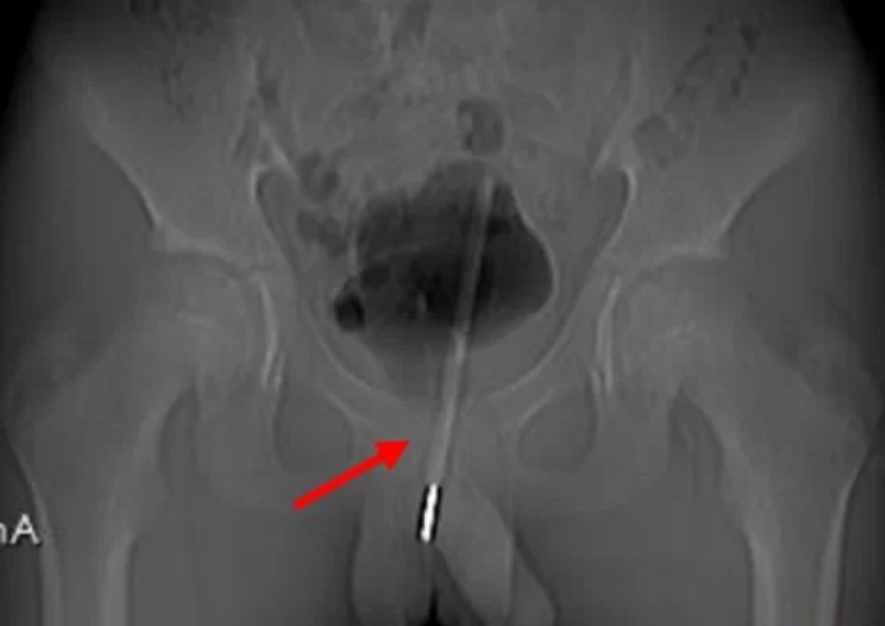

O menino estava sentindo dores por cerca de nove horas e foi levado ao hospital onde fez um raios-X que revelou que o termômetro havia sido inserido tão profundamente no trato urinário que na verdade havia entrado na bexiga do menino.

A extração o objeto foi feito pela bexiga da criança por meio de uma cirurgia. E equipe medica fez um pequeno orifício cirúrgico no tecido até a bexiga, que armazena a urina, e inseriram pequenas ferramentas para manipular o termômetro no ângulo e na posição corretos para retirá-lo pelo buraco criado.